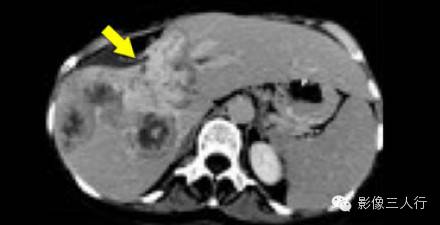

下图是另一例子胆管癌多发病变。注意,收缩和延迟强化的肿瘤内的纤维结构。

动脉期和延迟期胆管癌多发肿块引起肝包膜收缩。